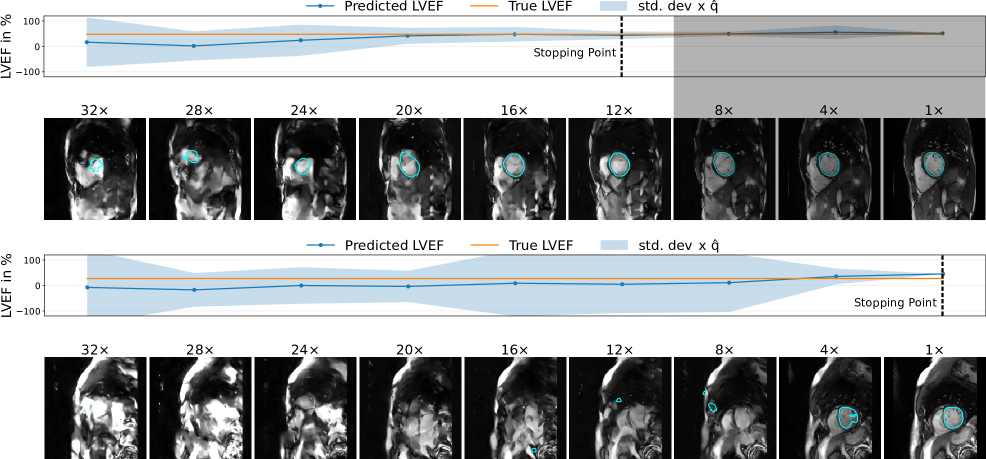

4.3 Qualitative Results

To provide a qualitative understanding of our dynamic stopping mechanism, Figures 4 and 5 show representative cases of both early and late scan terminations. Each figure visualizes the evolution of the reconstruction, segmentation, and the downstream metric along with its calibrated uncertainty as more k-space data is acquired. As expected, we observe a consistent trend across all examples: as the acquisition progresses, reconstruction quality and segmentation accuracy visibly improve. Moreover, the prediction uncertainty decreases the more k-space data is being collected. Additional reconstruction examples are displayed in Figure 6 and 7. Concurrently, the downstream metric estimation converges toward the ground truth value while the corresponding uncertainty bands narrow. Crucially, instances of high uncertainty consistently correspond to visible artifacts, segmentation errors, and larger deviations in the final metric, confirming that our uncertainty estimates effectively track acquisition quality.